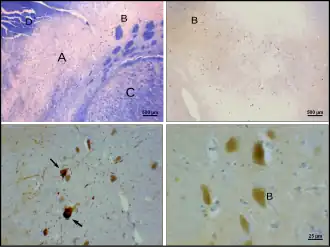

Substantia nigra highlighted in red. | |

Section through superior colliculus showing substantia nigra. | |